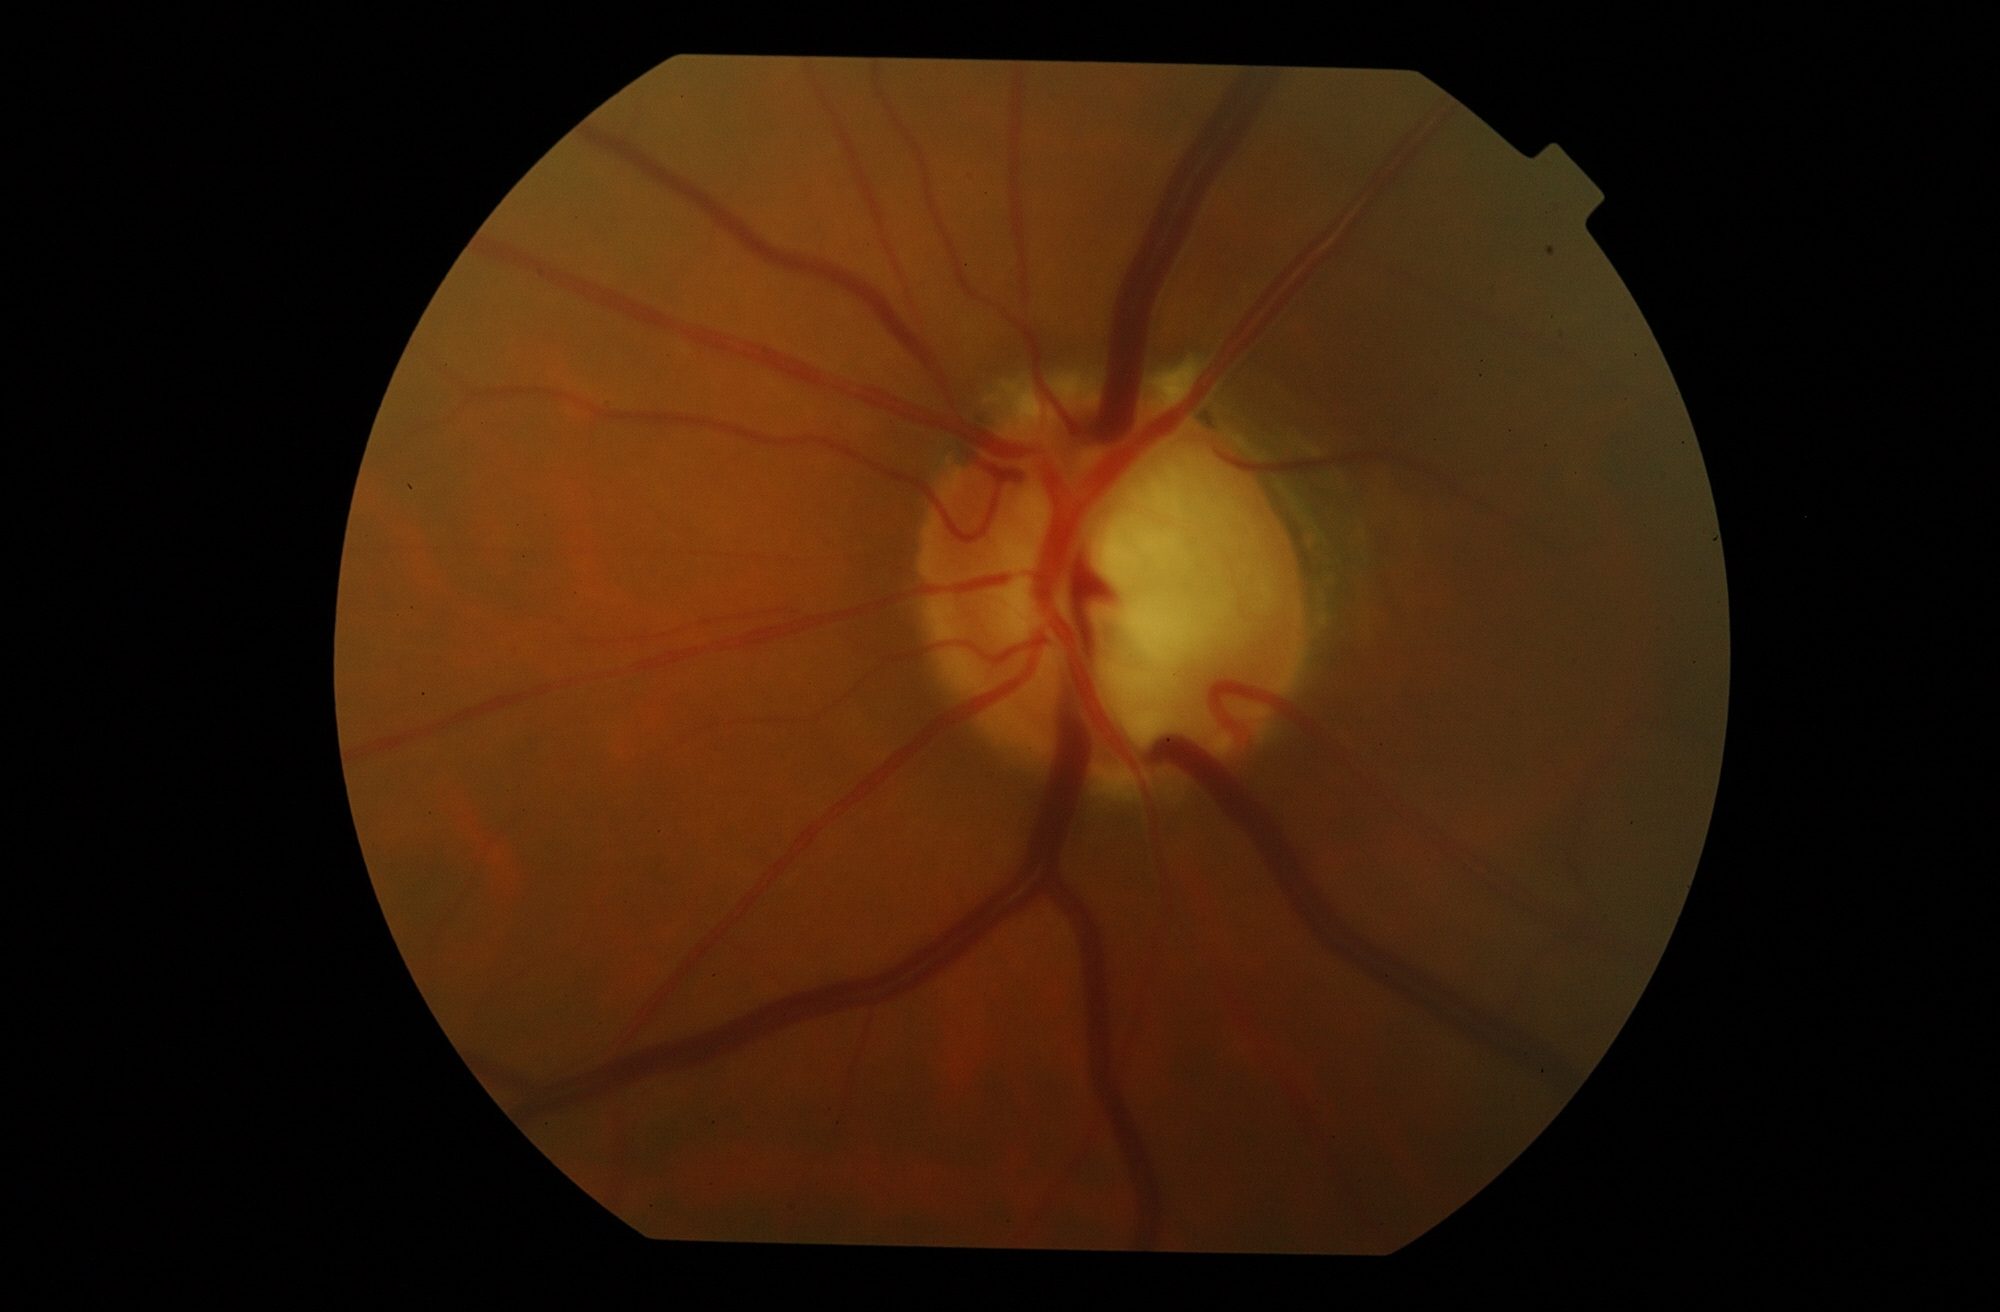

Es una enfermedad que daña las fibras del nervio óptico (neuropatía) dándole un aspecto característico y se acompaña por una alteración de la visión lenta pero irreversible.

→ Leer más